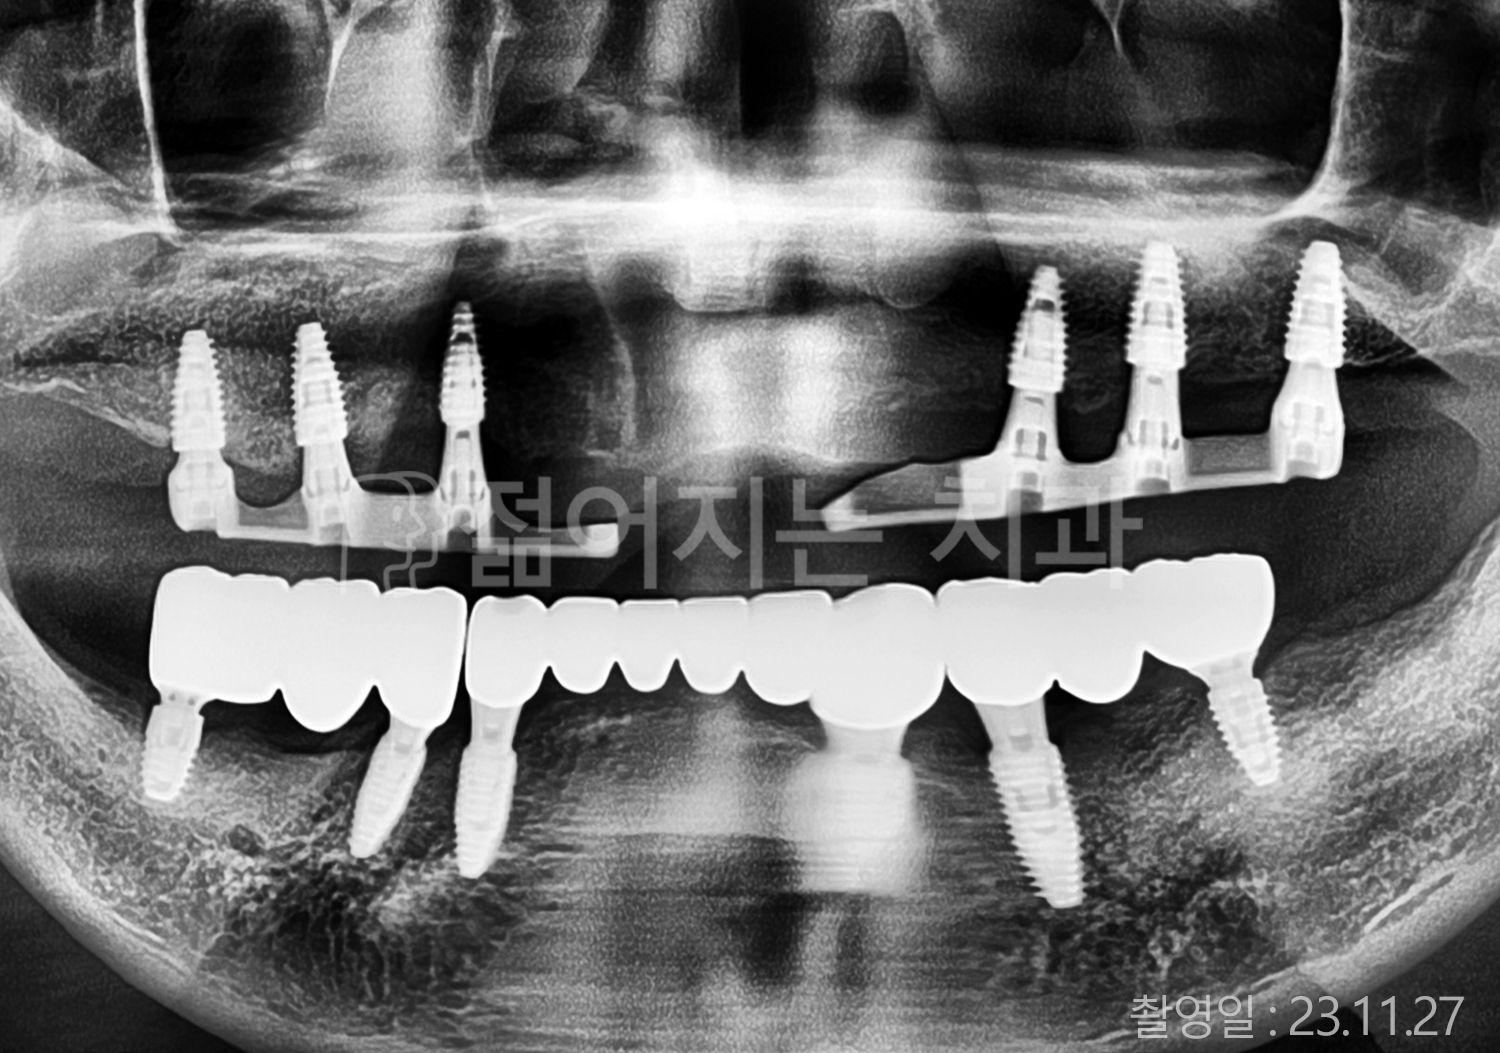

• 40대 전체치아 10개 이상 임플란트

• 50대 전체치아 10개 이상 임플란트